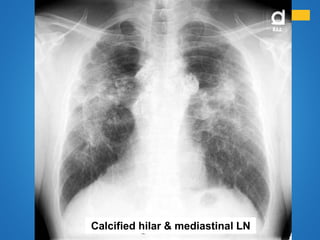

Calcified hilar & mediastinal LN